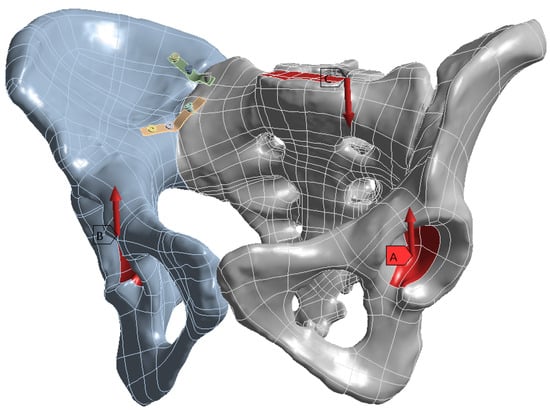

Biomechanical Comparison of Three Fixation Constructs for Tile Type C1.2 Pelvic Ring Fractures: A Finite Element Analysis

by Adrian Claudiu Carp, Bogdan Veliceasa, Dmour Awad, Alexandru Filip, Mihaela Perțea, Norin Forna, Bogdan Puha, Ștefan Dragoș Tîrnovanu, Mihnea Theodor Sîrbu, Silviu Dumitru Pavăl and Paul Dan Sîrbu

Life 2026, 16(2), 336; https://doi.org/10.3390/life16020336 - 15 Feb 2026

Fractures of the pelvic ring are among the most severe injuries in orthopaedic practice and Tile type C lesions are characterized by complete disruption of the posterior arch with both vertical and rotational instability. The optimal construct for posterior ring fixation remains a matter of debate. The aim of this study was to compare, by means of finite element analysis, the biomechanical performance of three different methods of osteosynthesis for Tile type C1.2 pelvic ring fractures: a transiliac plate, one iliosacral screw and two anterior reconstruction plates on the sacroiliac joint. A three-dimensional model of an intact pelvis was reconstructed from computed tomography images of a healthy adult male. A Tile type C1.2 injury pattern was created virtually, and three fixation constructs were designed in Ansys SpaceClaim according to manufacturer specifications. All materials were assumed to be homogeneous, isotropic and linearly elastic. Vertical loads of 400 N and 800 N were applied to the sacral endplate to simulate partial and full weight bearing, while the acetabular regions were constrained to represent standing stance. In this study, mechanical stability was operationally defined as resistance to global displacement under applied vertical load, with lower displacement indicating higher construct stiffness. Construct stiffness, total deformation and von Mises stress were assessed for bone and implants. For both loading conditions, the iliosacral screw construct showed the lowest overall displacement and provided the greatest stiffness. The transiliac plate construct presented larger displacements, whereas the anterior reconstruction plate construct provided intermediate stability with higher stresses at the sacroiliac joint. Among the analyzed constructs, the iliosacral screw provided the greatest stiffness and lowest overall displacement, suggesting superior mechanical performance under vertical loading conditions. Full article

Figure 1